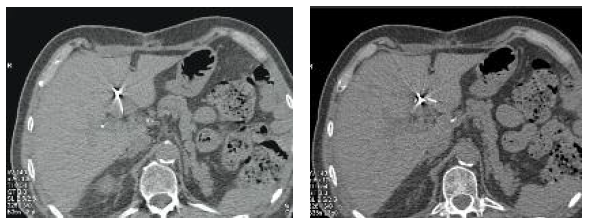

patient using image guidance (Figures 1-4). Most frequently, ultrasound and

Figure 3 and 4. Computed Tomography Images Demonstrate Exact Placement of Radiofrequency Needle